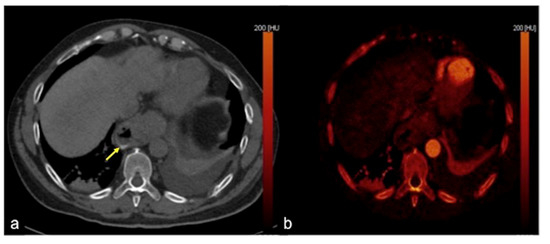

| Haemobilia (Figure 32) | Melaena, haematemesis, biliary colic, jaundice, or massive bleeding in a patient with a history of blunt or iatrogenic abdominal trauma. | Presence of blood in the gallbladder and biliary tree. |